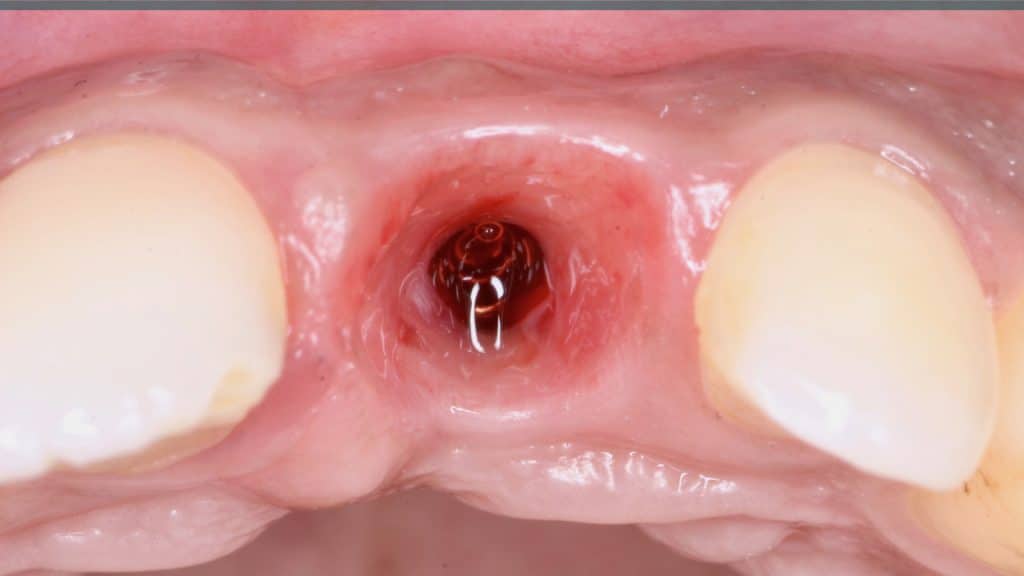

Immediate post-op